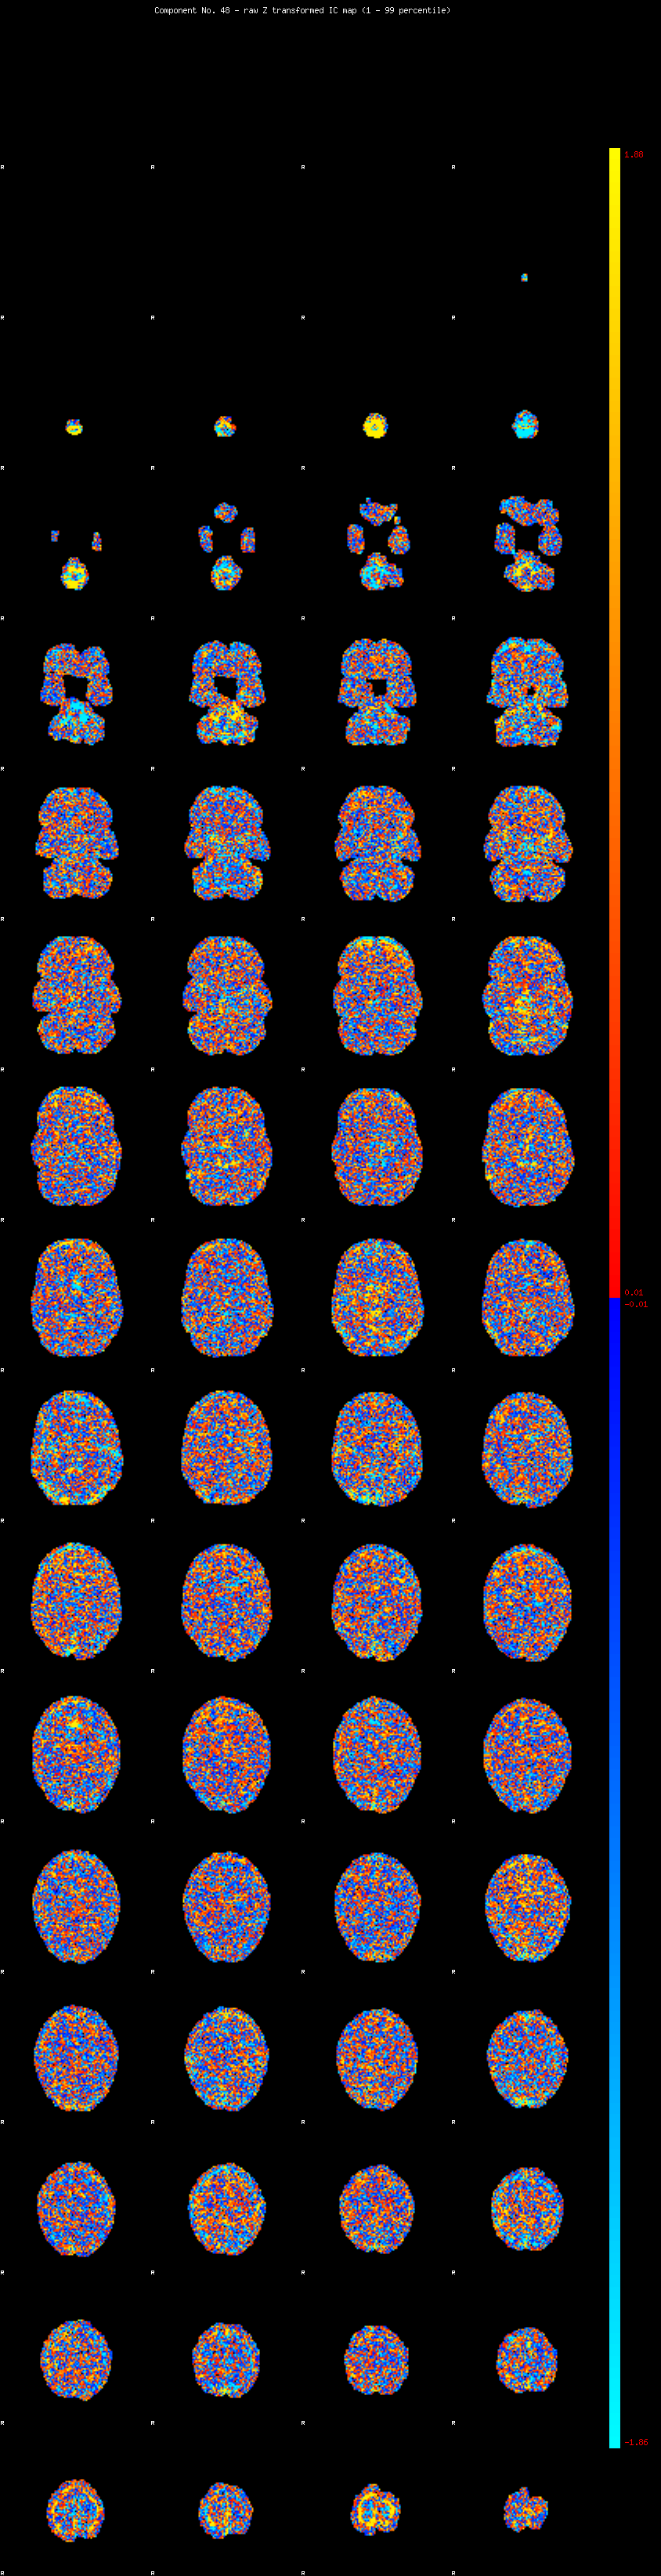

IC_48 Mixture Model fit

Means : -0.000000 2.620656 -2.575280

Vars : 1.000000 2.570731 2.431624

Prop. : 0.965580 0.017733 0.016687